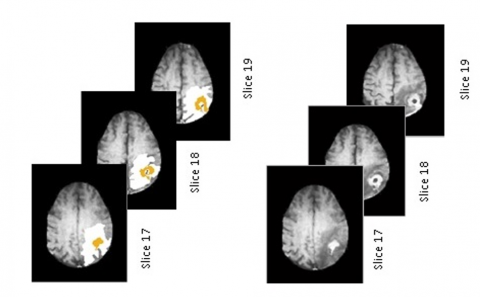

The outcomes of this investigation entail the documentation of two instances involving patients afflicted with glioblastoma. Two magnetic resonance examinations were acquired for every patient, specifically, the first within a period of 90 days subsequent to the conclusion of chemoradiotherapy and the second at the stage of disease progression, as illustrated in Figure 4 and Figure 5.

Figure 4. Graph cuts segmentation of tumor region for instance 1

Figure 5. Graph cuts segmentation of tumor region for instance 2

Finally, the tumor region “maskTumor” result obtained by graph cut segmentation is smoothed and enhanced by a second segmentation based on a standard FCM algorithm. The results of this inquiry involve recording two cases of patients suffering from glioblastoma, the first within a period of ninety days subsequent to the conclusion of chemoradiotherapy and the second at the stage of disease progression, as illustrated in Figures 6 and 7.

Figure 6. FCM-based enhancement of the tumor region for case 1

Figure 7. FCM-based enhancement of the tumor region for case 2